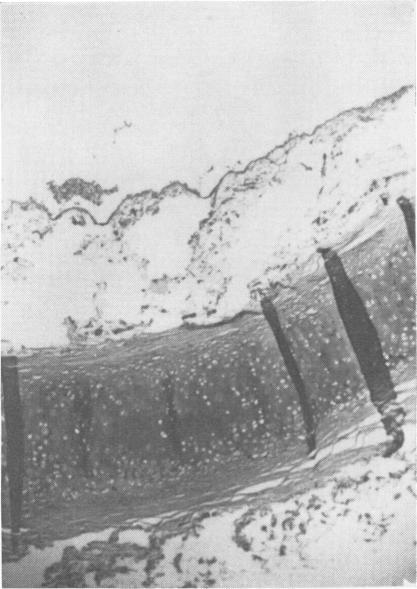

78-86. Seven cases of ammonia gassing are described with follow-up for five years of the six survivors and the post-mortem findings of the fatal case. All the survivors attributed continuing symptoms to the gassing. The study failed to demonstrate permanent ill effects in the one case of mild exposure. Of the more serious cases one has stopped smoking and taken up physical training teaching. He now has above average lung function. Two serious cases who continued to smoke have the lung function abnormalities expected from their smoking. In the other two seriously exposed cases, who also continued to smoke, there is a persistent reduction in ventilation and gas transfer which seems to be due to the ammonia gassing. The post-mortem findings in the fatal case showed acute congestion and oedema of the mucosa of the respiratory tract, the bronchial walls being stripped of their lining epithelium and the alveoli stuffed with red blood cells and oedema fluid.

78 - 86. 本文描述了7例氨气中毒病例,对6名幸存者进行了为期5年的随访,并给出了 fatal case的尸检结果。所有幸存者都将持续出现的症状归因于氨气中毒。该研究未能证明轻度暴露的那例病例有永久性不良影响。在病情较重的病例中,有一人已戒烟并开始从事体育教学工作。他现在的肺功能高于平均水平。另外两名继续吸烟的病情较重的病例,其肺功能异常符合他们吸烟的情况。在另外两名同样继续吸烟的严重暴露病例中,存在持续的通气和气体交换减少,这似乎是由氨气中毒导致的。致命病例的尸检结果显示,呼吸道黏膜急性充血和水肿,支气管壁的内衬上皮脱落,肺泡充满红细胞和水肿液。